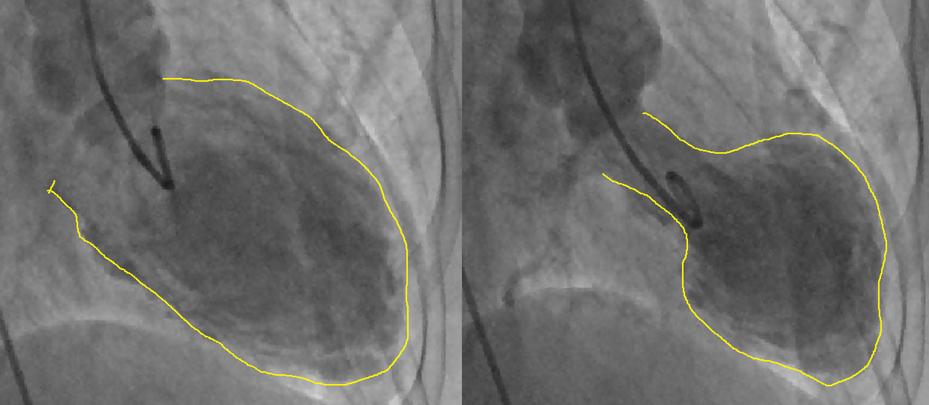

Takotsubo cardiomyopathy (TTC) is thought to be largely a transient condition caused by emotional triggers such as bereavement, a serious accident or other very stressful events. It can lead to heart failure and symptoms that mimic a heart attack. Often those affected will make a full recovery, though some have lasting problems. Takotsubo means octopus pot in Japanese, and the shape of the heart is said to look like such a pot.

The heart develops an octopus pot look (right)